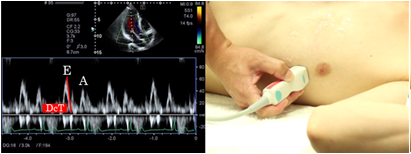

Left ventricular inflow pattern

The left ventricular inflow pattern is recorded in the apical longitudinal view or the apical 4 chamber view. Try your best to set a view in which the Doppler beam is in parallel with the left ventricular inflow. The position of the sample volume is set at the distal tip of the mitral valve. The left ventricular inflow pattern is used for measurement of early diastolic waves (E-waves), atrial systole wave (A-wave), and deceleration time of E-wave (DcT). You must be careful because the velocity of E- and A-waves and the E/A ratio change when the position of the sample volume is changed.